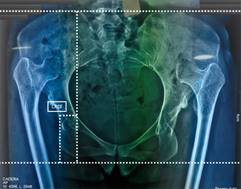

Esta presentación tiene como objetivo describir el caso clínico de una paciente femenina de 29 años y la técnica quirúrgica empleada en la ATC asociada a osteotomía de acortamiento supracondílea en luxación de cadera inveterada Crowe 4 (Figura 1), utilizando implantes no cementados copa TrinityMR (Corin) y vástago MiniHipMR (Corin) con un par de fricción cerámica-polietileno con fijación distal (placa LC-LCP 4 orificios).

Figura 1: Radiografía anteroposterior de pelvis y medición radiográfica para obtener centro de rotación de cabeza femoral nativo (CRCF).

Al tratarse de una luxación inveterada bilateral Crowe 4, el objetivo de esta cirugía es restaurar el centro de rotación de la cabeza femoral (CRCF) nativo del acetábulo, por lo que se realizan mediciones preoperatorias para obtener dicho centro, tomando como referencia la línea interilíaca e interisquiática (Figura 1), istmo femoral y metáfisis para tomar en consideración el tamaño de los implantes, como primera instancia se propuso realizar osteotomía femoral supracondílea, con la finalidad de utilizar un vástago corto de apoyo metafisario.